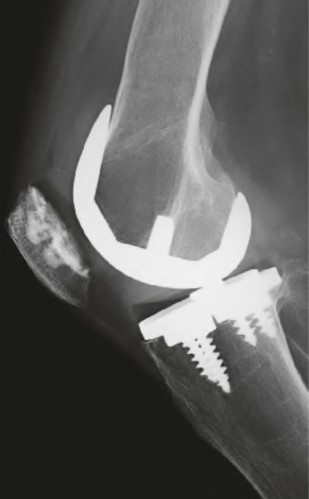

A 70-year-old female presents 6 months post-total knee arthroplasty with an inability to actively extend her knee. Examination reveals a palpable defect at the superior pole of the patella. What is the most appropriate surgical reconstruction option for a chronic quadriceps tendon rupture following TKA with inadequate remaining tissue?

Explanation